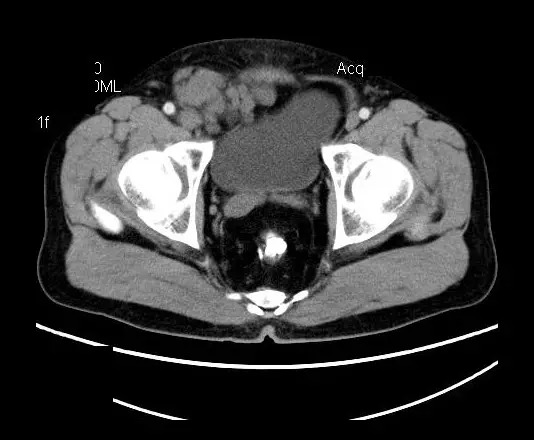

【影像表现】

盆腔右前侧及邻近腹股沟区可见多发大小不等的聚集生长的结节影,病灶呈软组织密度,边缘尚规整,分界尚清,增强扫描可见不均匀强化。膀胱局部受压,盆腔未见明显肿大淋巴结影。